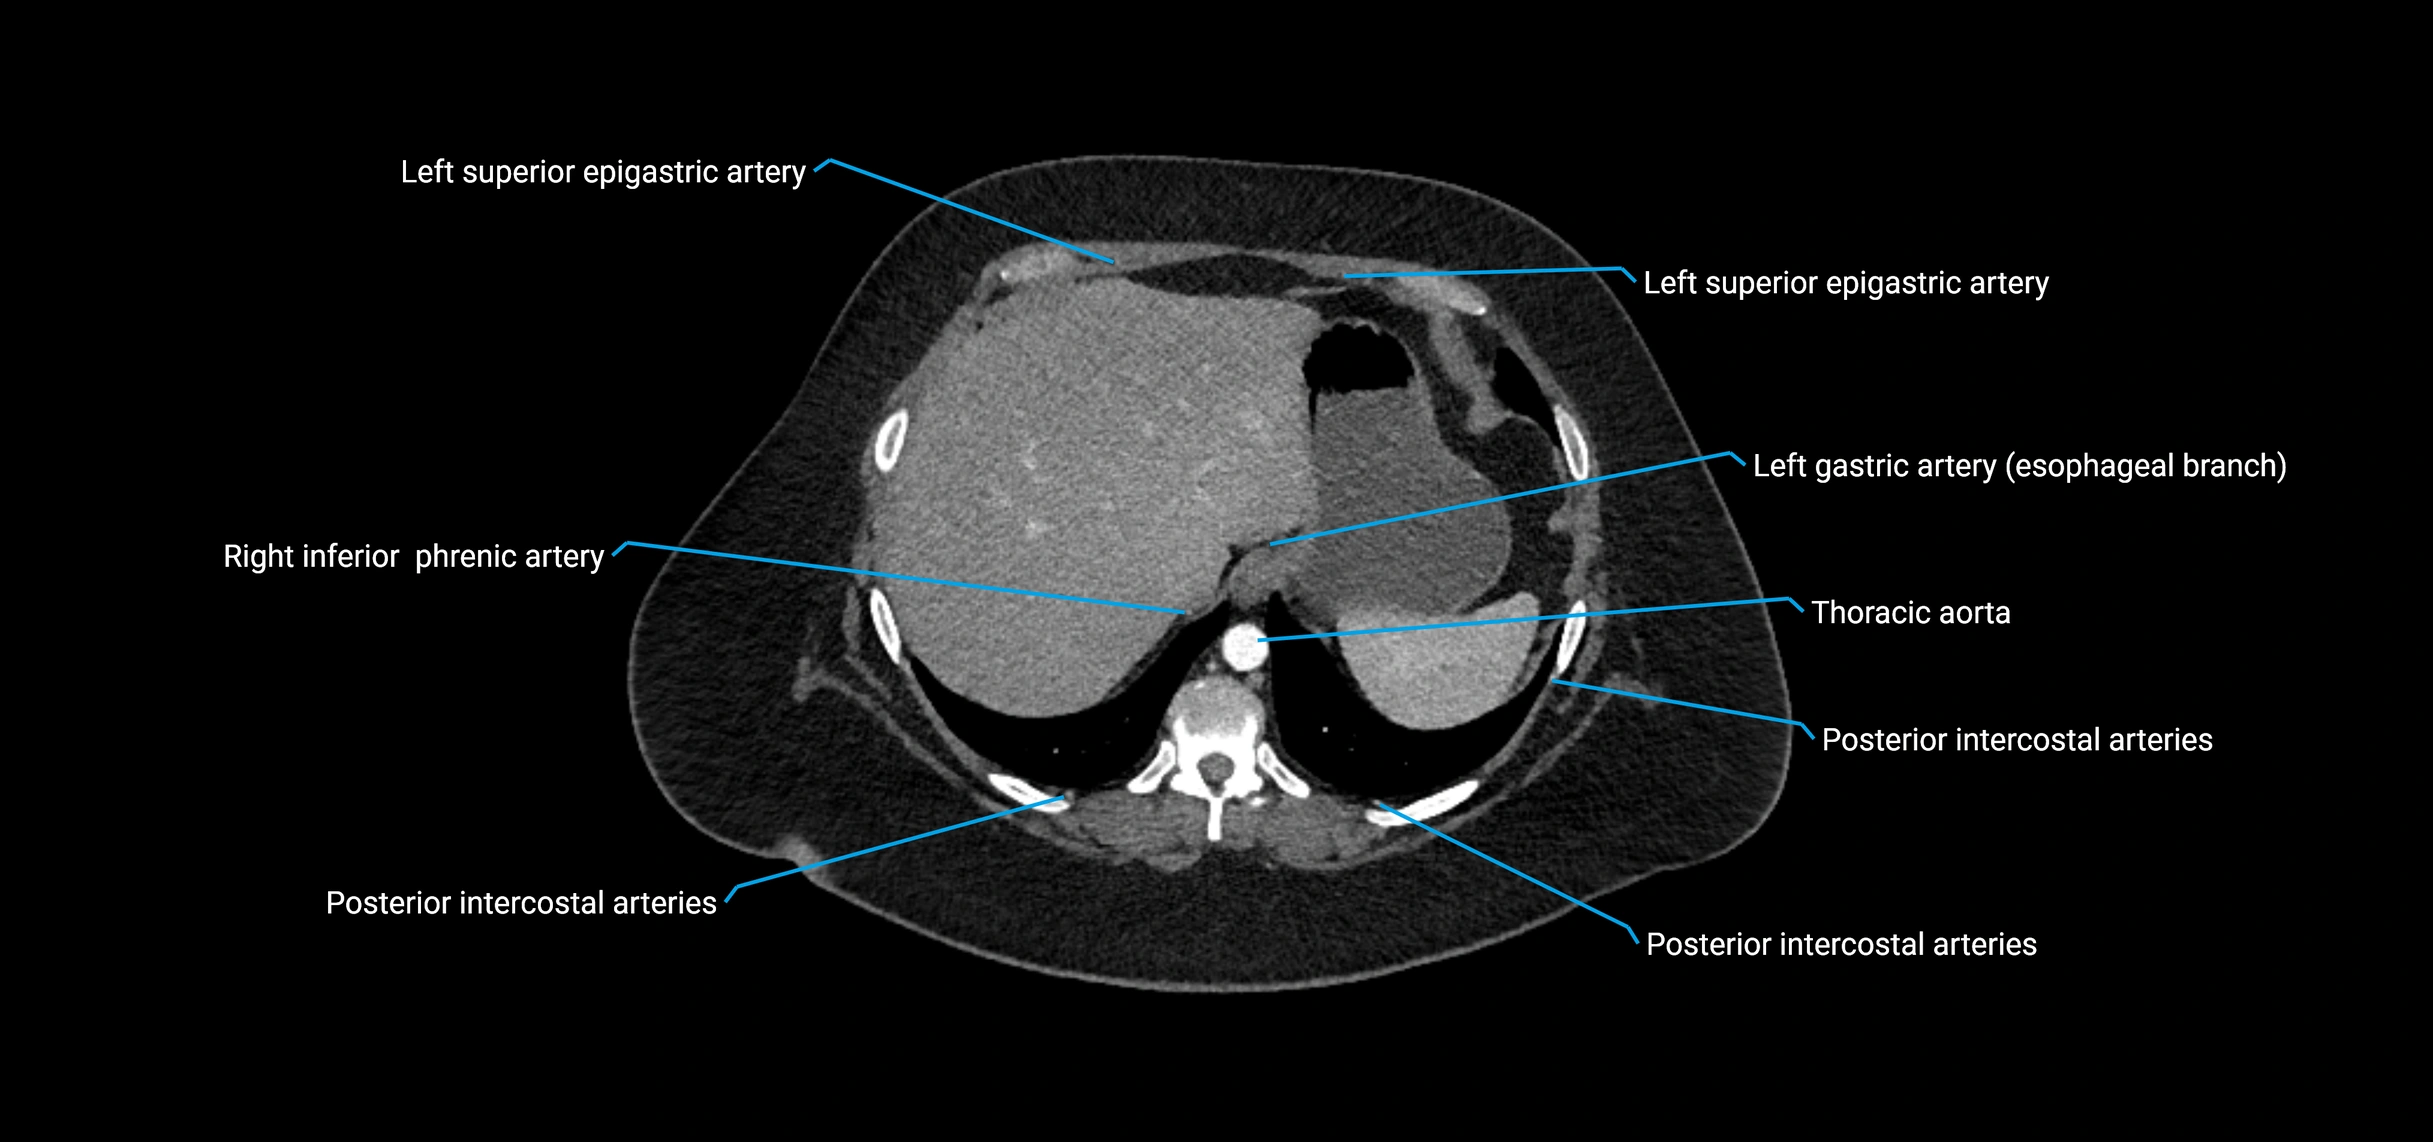

CT images

image

Contrast-enhanced CT (CTA):

• Gold standard for abdominal aortic imaging

• Provides excellent detail of lumen, wall, aneurysm, thrombus, and branch vessels

• Multiplanar and 3D reconstructions help in aneurysm measurement, stent graft planning, and dissection evaluation